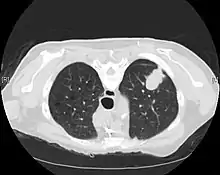

CT scan- adenocarcinoma of the left lung

The majority of lung cancers can be characterized as either small cell lung cancer (SCLC) or non-small cell lung cancer (NSCLC). Lung adenocarcinoma is one of the three major subtypes of NSCLC, which also include squamous carcinoma and large cell carcinoma.[15]

CT imaging provides better evaluation of the lungs, with higher sensitivity and specificity for lung cancer compared to chest radiograph (although still significant false positive rate[27]). Computed tomography (CT) that is specifically aimed at evaluating lung cancer includes the chest and the upper abdomen. This allows for evaluation of other relevant anatomic structures such as nearby lymph nodes, adrenal glands, liver, and bones which may show evidence of metastatic spread of disease.[4] Indeed, the US Preventative Services Task Force recommends annual screening with low-dose CT in adults aged 55 to 80 years who have a 30 pack-year smoking history and currently smoke or have quit within the past 15 years, with certain caveats (see Lung cancer screening).[28]